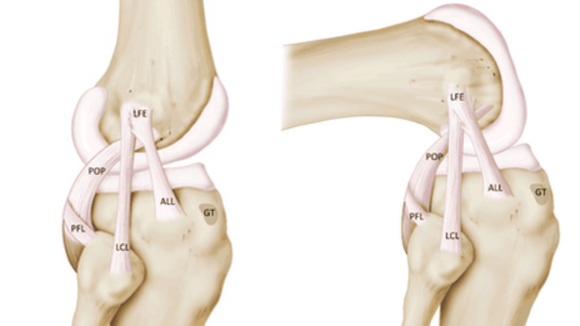

Ligamenti kolena se mogu podeliti na tri grupe, to su lateralni ligamenti kolena ( sa leve i desne strane kolena), zadnji ukršteni ligamenti kolena (unutar zgloba) kao i prednji ligament čašice ( patelle). Ligamenti su debeli vlaknasti snopovi. Njihova funkcija je da obezbede stabilnost kolena, prevenciju povreda, drže kosti zajedno, kontrolišu kako se koleno kreće i pružaju potporu telu. Pokrete koji ovi ligamenti omogućavaju kolenu jesu opružanje, pregibanje i ograničenu rotaciju.

Koleno čine četiri kosti: femur ( butna kost), tibia, fibula (golenjača) i patella ( čašica).

Prednji ukršteni ligament sprečava butnu kost od klizanja unazad (ili potkolenicu da klizi napred na butnu kost).

Zadni ukršteni ligament sprečava butnu kost od klizanja napred na potkolenicu.

Lateralni ligamenti sprečavaju butnu kost od klizanja sa jedne na drugu stranu.